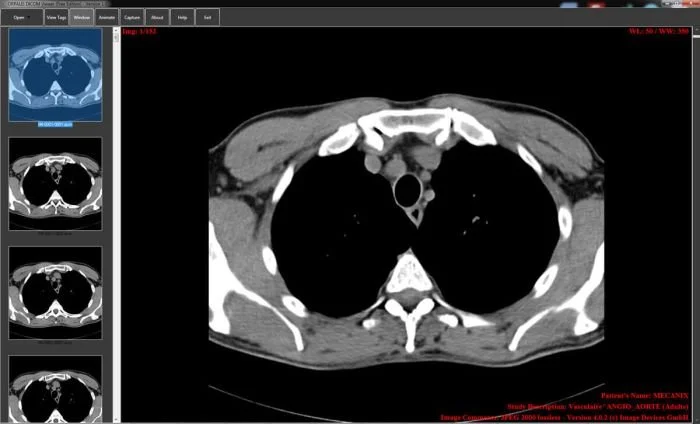

Стандарт позволяет организовать цифровую связь между различным диагностическим и терапевтическим оборудованием, использующимся в системах различных производителей. Рабочие станции, Компьютерные (КТ) и Магнитно-резонансные Томографы (МРТ), микроскопы, УЗ-сканеры, общие архивы, хост-компьютеры и мэйнфреймы от разных производителей, расположенные в одном городе или нескольких городах, могут "общаться" друг с другом на основе DICOM с использованием открытых сетей по стандартным протоколам, например TCP/IP.

Популярные программы для просмотра DICOM-файлов (Windows, macOS, iOS, Android и Linux)

Видео-обзор лучших программ для просмотра DICOM-файлов

XA — Рентгеновская ангиография (X-Ray Angiography)